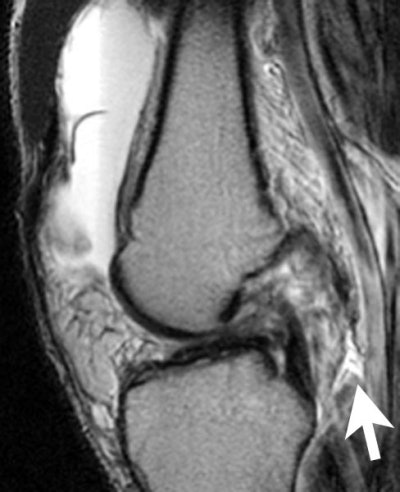

Sagittal fast spin echo, T2-weighted WI with fat saturation through the chronically torn anterior cruciate ligament. As is often seen in chronic tears, the ACL has a flat course. Note the rupture of the joint capsule posteriorly (arrow), a component of the acute injury. |